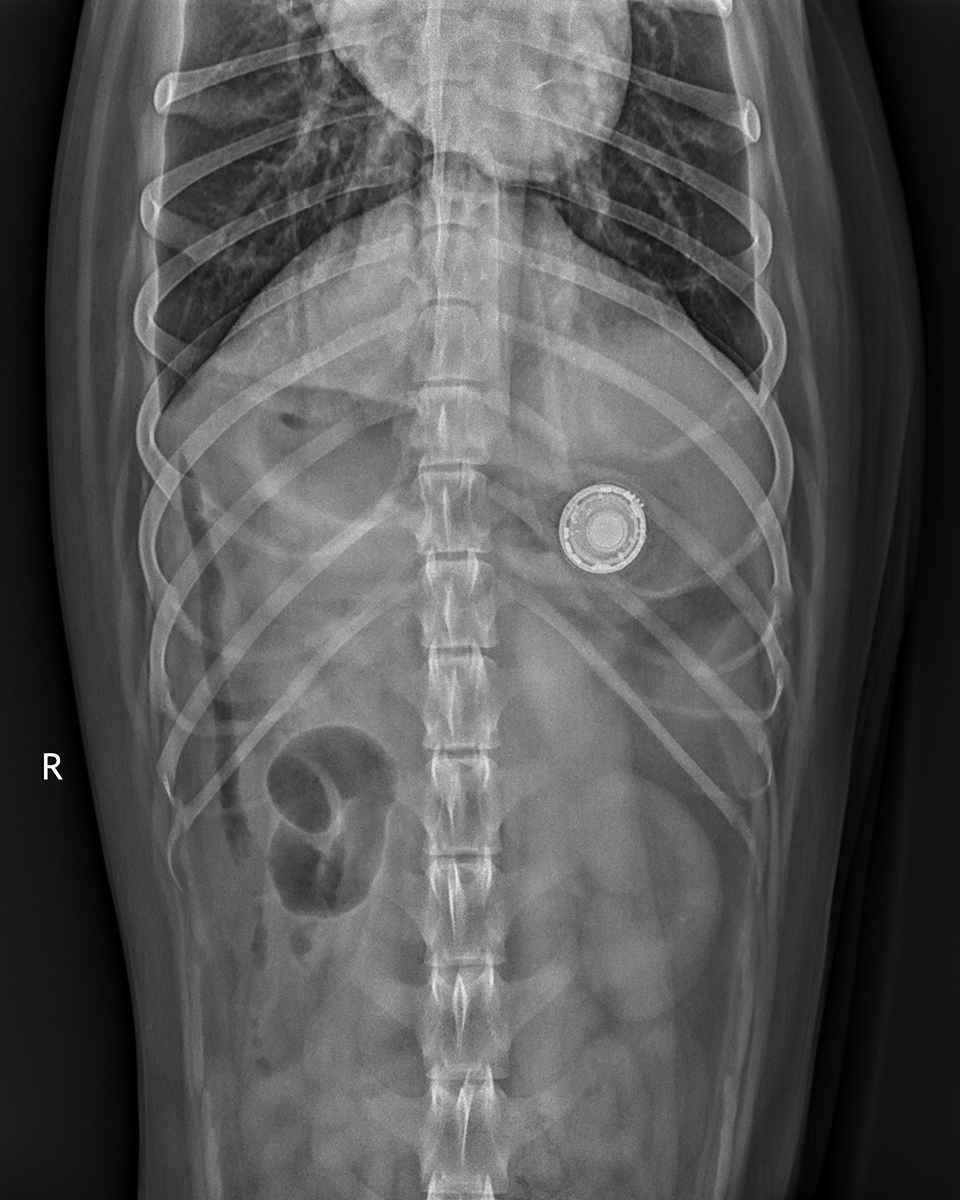

И такая история далеко не одна. Владельцы собак на Reddit активно делятся своими рассказами, а ветеринар из Луизианы рассказал журналистам о том, что за последние полтора года он шесть раз лично сталкивался с подобными случаями. Во всех этих случаях изначально AirTag крепилась к ошейнику. Специалисты отмечают, что иногда такая ситуация может привести к необходимости хирургического вмешательства. Особенно, если корпус метки будет повреждён.